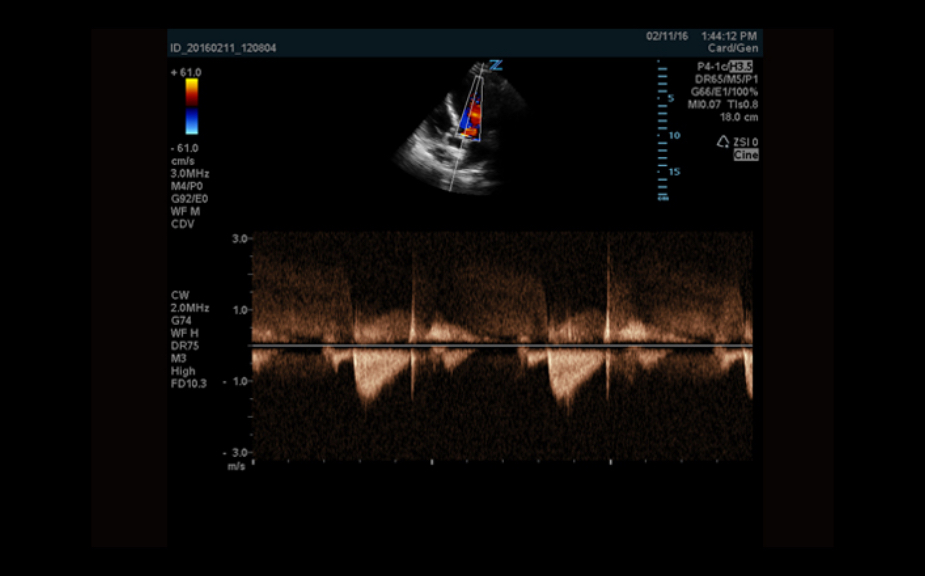

Equipado con software patentado con base en tecnolog├Ła ZONE?Sonography? (ZST),?el Z.One PRO proporciona toma de im├Īgenes Doppler y Modo-B detalladas ├│ptimamente para pacientes, sin importar la complexi├│n del cuerpo, ayudando a asegurar un diagn├│stico confiable.

- Doppler CW con transductores auxiliares

El Z.One PRO est├Ī dise?ado bas├Īndose en ZONE Sonography Technology, una arquitectura de formaci├│n de im├Īgenes innovadora y registrada que adquiere y procesa informaci├│n ac├║stica hasta 10 veces m├Īs r├Īpido que los m├®todos de formaci├│n de haces convencionales.

La plataforma de toma de im├Īgenes por ultrasonido Z.One PRO ofrece una familia completa de transductores de peso ligero que incorporan capacidades de banda ancha extendida y flexibilidad multifrecuencia que proporciona una claridad excepcional y una resoluci├│n de detalle mejorada incluso en las mayores profundidades. El transductor C4-1 puede penetrar a trav├®s del campo de visi├│n mientras mantiene una resoluci├│n espacial y de contraste excepcional.